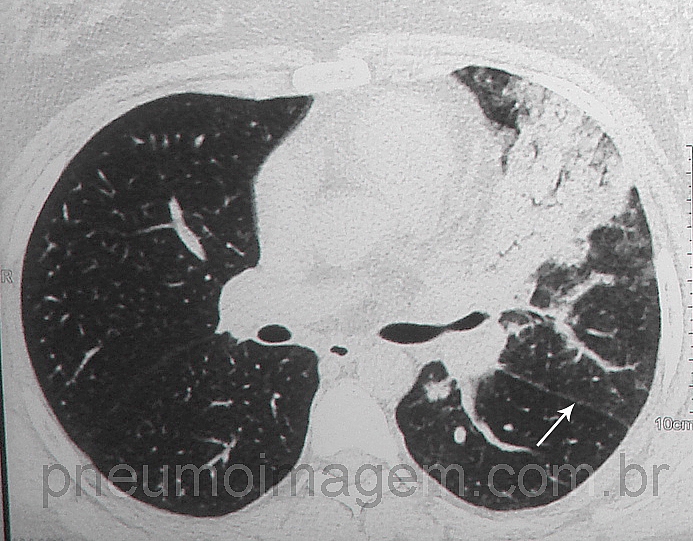

Veja imagens de pneumonia causadas pelo Influenza no PneumoImagem, clique aqui.